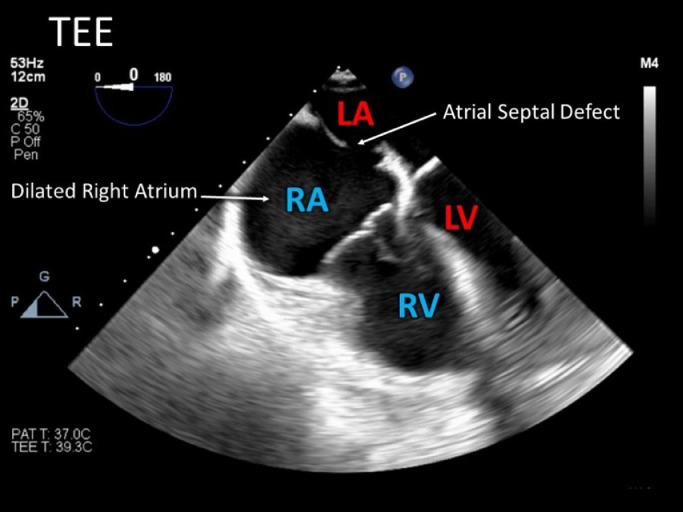

Traumatic atrial septal defect diagnosed by bedside point-of-care ultrasound.

Atrial septal defects (ASD) caused by traumatic events, specifically blunt cardiac trauma, are considered an infrequent occurrence, yet their true prevalence has been difficult to ascertain. The general lack of knowledge is likely due to the pathology being severely understudied. We present the case of a 21-year-old male who was diagnosed with ASD following a motor vehicle accident. Initial assessment utilizing the point-of-care ultrasound (POCUS) technique - focused assessment with sonography for trauma (FAST) was found to be negative for free intraperitoneal or pericardial fluid. Subsequent computed tomography displayed multiple injuries but agreed with the FAST exam findings of no fluid within the abdomen or pericardium. Later in the patient's care a dedicated POCUS transthoracic echocardiogram was performed which identified right sided heart dilatation. The patient was managed in the intensive care unit (ICU) for an extensive period but recovered sufficiently to be discharged. The plan was to repair the ASD on a non-emergent basis. This case highlights the importance and diagnostic utility of bedside POCUS.